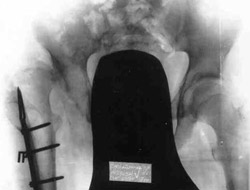

Schanz-Ilisarov's operation with elongation of hip.Results of treatment.

Results of treatment.